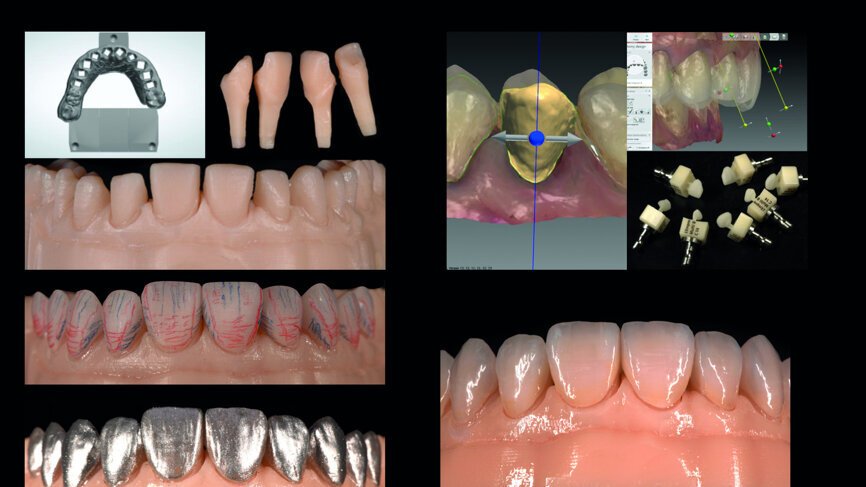

Fig. 13: Analogue workflow (refractory dies, built-up veneers, adjustments, staining/glazing).

Fig. 14: Digital workflow (3-D printed model, CAD/CAM veneers, adjustments, staining/glazing).

Provisionalisation was executed digitally, using Telio CAD (Ivoclar Vivadent) in the Wieland Select CNC milling machine. The design was performed with the 3Shape DentalDesigner 2015 software (Figs. 12a & b). Two sets of final restorations were fabricated. The set of feldspathic veneers was fabricated on a stone model using IPS Style (Ivoclar Vivadent), while IPS Empress CAD Multi (Ivoclar Vivadent) was used for the digitalset (Figs. 13 & 14). Both sets were examined intraorally with a try-in paste to compare the optical properties of the feldspathic and the CAD/CAM veneers (Figs. 15a–c).